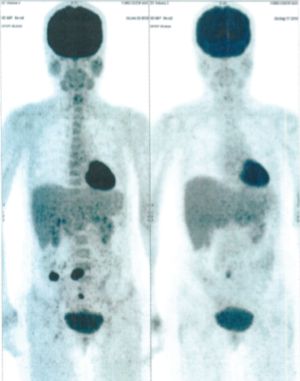

Below are some of the cases, from more than 80 cases we have treated so far with good results. When reading the PET/CT scans, the picture on the left is before treatment, and the picture on the right is after treatment. The intensity of black represents the activity of the cancer, but some black areas are not cancer: brain, heart, radioactive urine in bladder. For the heart, the intensity of black depends on the number of hours of fasting: if more than 10 hours, the heart is not even black, but if fasting is less than 6 hours, it is very black. The intensity of black in the brain can be variable in different scans depending on the brain activity at the time of the scan. The intensity of black in the radioactive urine can also be variable due to the hydration of patients and the time of injection of diuretic.

CASE NO: 34 (PERIPHERAL T-CELL LYMPHOMA)

A 50+ year old female has recurrent Peripheral T-Cell Lymphoma that failed all treatment, and it has spread to lymph nodes in the axillary and mediastinal region, and to the lungs. The specialists gave her about 3 months to live. After just one treatment, the axillary/mediastinal nodes and the lung lesions are gone. One set of pictures shows the lymph nodes, and the other set of pictures show lung lesions. The picture on top is BEFORE TREATMENT, and the picture below is AFTER TREATMENT.

CASE NO: 34 AFTER TREATMENT